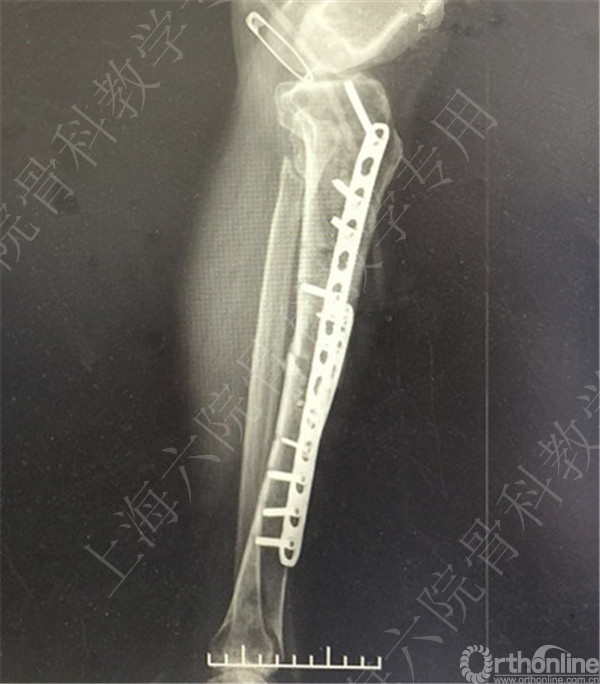

术后X线摄片示:骨折对位对线欠佳,稍成角。

患者复查,X线摄片示:骨折对位对线差,左胫骨立线欠佳,成角。

医方第一次跟换内固定术中,未纠正左胫骨立线,骨折对位对线差,未纠正成角,导致术后内固定失效,骨折成角变大。医方存在手术方式不当,手术操作不当,术后并发症观察、处理不当,对疾病评估不足,告知缺陷等过失。